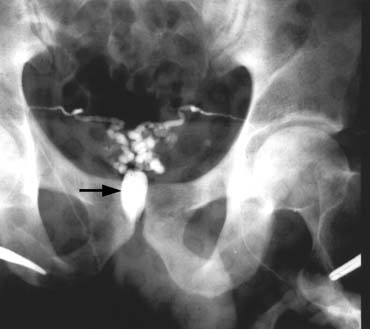

Digital rectal examination may reveal a midline cystic structure. Transrectal sonography has revolutionized the diagnosis and treatment of ejaculatory duct obstruction. A midline cystic lesion or dilated ejaculatory ducts and seminal vesicles can be visualized sonographically. Transrectal ultrasound-guided aspiration of the cystic or dilated ejaculatory ducts or seminal vesicles can be performed.52 The aspirate is examined microscopically and if motile sperm are found, they can be cryopreserved and 2 to 3 mL of indigo carmine diluted with water-soluble radiographic contrast is instilled. If an x-ray confirms a potentially resectable lesion (Fig. 30), then transurethral resection of ejaculatory ducts (TURED) is performed without the need for previous vasography as the presence of sperm in the seminal vesicles indicates that at least one epididymis is patent and that the cyst or dilated ejaculatory duct communicates with a nonobstructed vas. The instillation of indigo carmine assists in localizing the opening of the ejaculatory duct and confirms when resection has successfully opened the obstructed system. Transrectal sonography with aspiration should be performed immediately before anticipated surgery and uses bowel prepartation and antibiotic prophylaxis.

Fig. 30. Both vasa are visualized after injection of contrast into only the right vas. The vasa empty into a common cavity, likely a mid-line ejaculatory duct cyst (arrow).